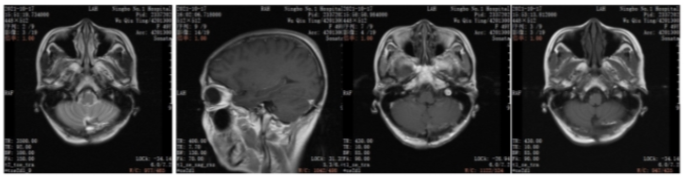

2021年6月颅脑增强MRI:左侧小脑占位,考虑转移瘤。

图2.颅脑增强MRI

2021年6月:出现头晕头痛1周,检查颅脑增强MRI:左侧小脑占位,考虑转移瘤。

2022年5月颅脑增强MRI:左侧小脑肿瘤切除术后改变。

疗效评价CR,继续维持曲妥珠单抗(汉曲优)+吡咯替尼+卡培他滨治疗方案

图3.颅脑增强MRI